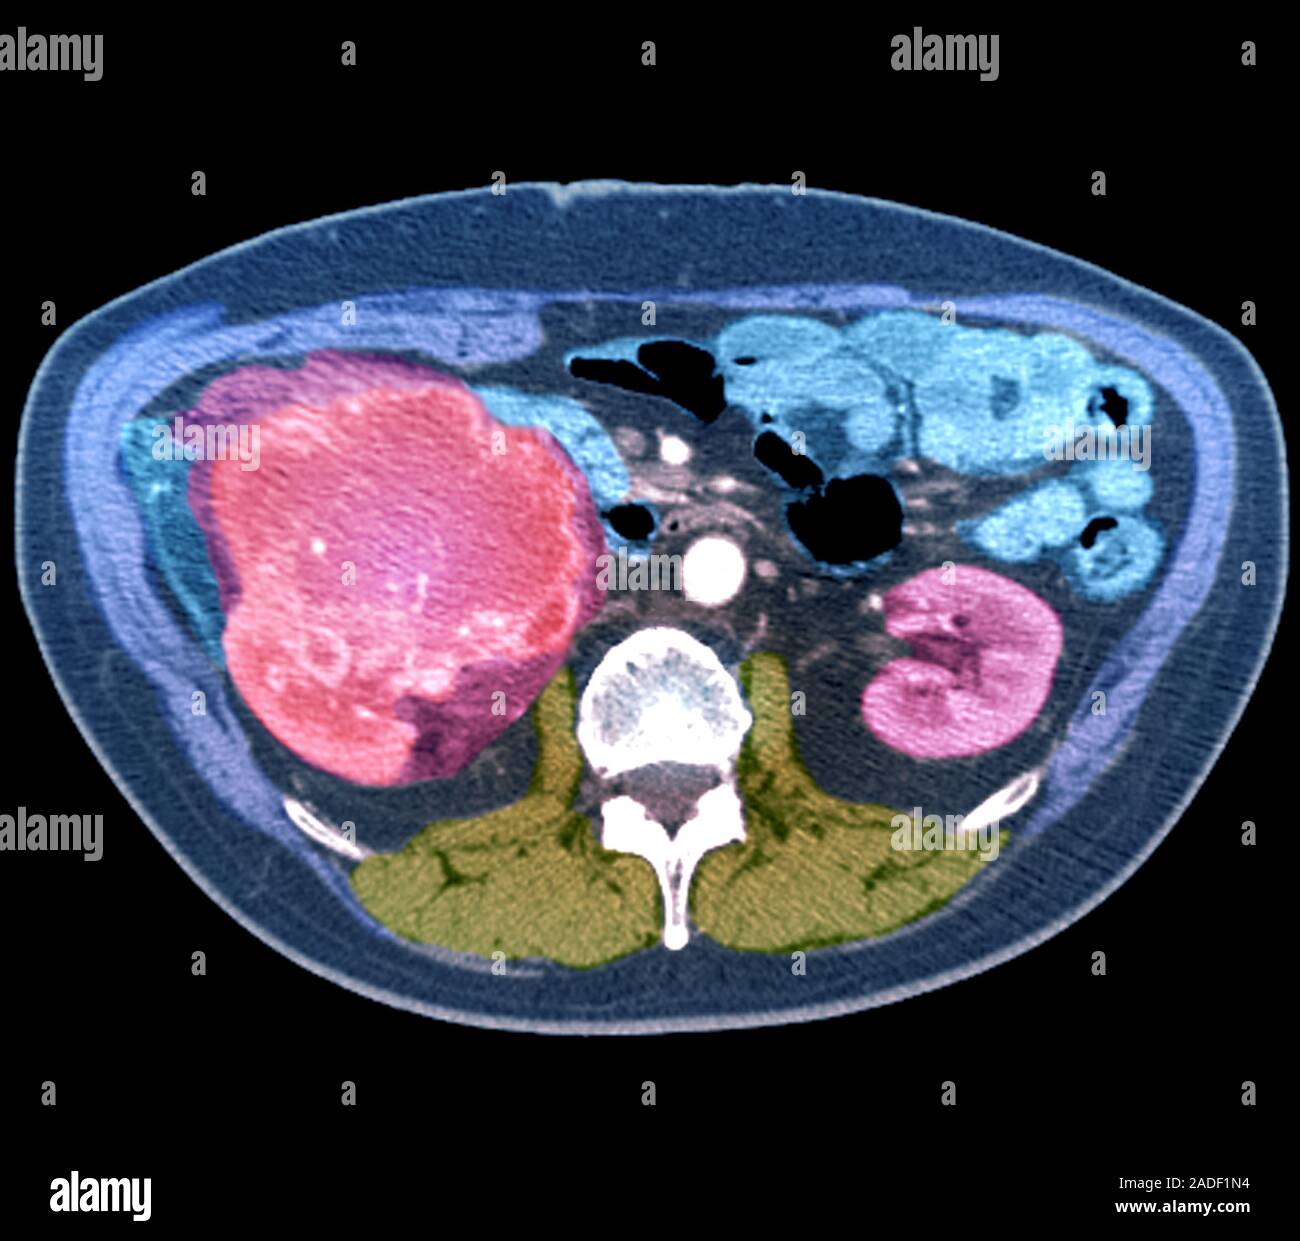

Kidney cancer, CT scan Stock Image C052/5644 Science Photo Library

Kidney cancer. Coloured axial computed tomography (CT) scan through the What Does Kidney Cancer Look Like On An Mri The stages of kidney cancer range from 1 to 4. If you develop kidney cancer symptoms, such as pain in your side, a lump near your kidney or blood in your pee, schedule an appointment with your. Scans, like an mri scan or ct scan; A stage 1 kidney cancer is small and confined to. If you've been told you. What Does Kidney Cancer Look Like On An Mri.